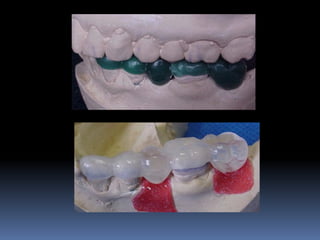

Modelos de estudo

Enceramento diagnóstico

Guia cirúrgica

Visão espacial do planejamento a

executar

•Articulados

•Projetar opções de terapêutica desde incisões,

delimitar áreas de reconstrução óssea,tipo de

prótese,número,distribuição, diâmetro dos implantes

•Compreensão do paciente

•Enceramento diagnóstico

•Guia cirúrgica